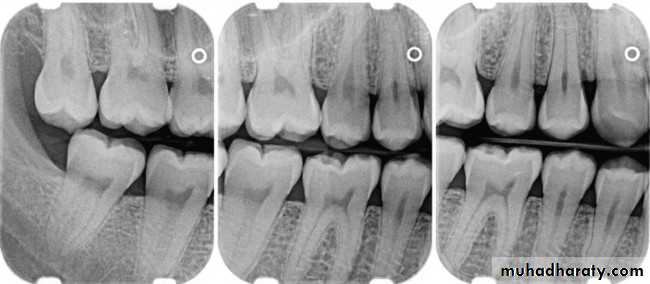

Although bone is one of the hardest tissue of human body, it's biologically a highly plastic tissue. Bone is sensitive to pressure and to tension which will cause bone remodeling which means resorption in certain areas and deposition of new bone in other areas.

Bone remodeling allows the teeth to be moved orthodontically.

Bone Remodeling (4 stages):

• Resorption: recruitment, migration, and activation of osteaoclasts causing bone resorption.• Reversal: cessation of resorption and disappearance of osteoclasts by apoptosis or migration , the site becomes occupied by mononuclear cells.

• Formation: osteoblasts recruitment, migration, differentiation and formation of new bone in resorption site.

• Resting: formation of new bone ceases and the surface is lined by a flattened layer of cells.